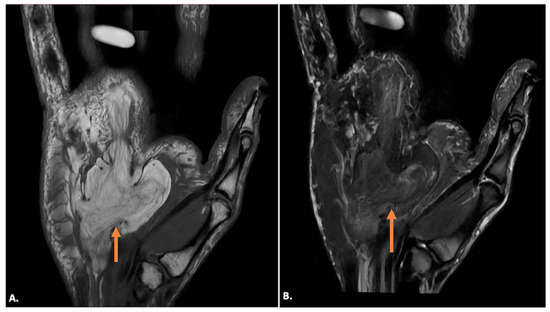

On MRI, ganglion cysts are well defined, hypointense on T1-weighted images, and hyperintense on T2-weighted images, reflecting their fluid content. Post-contrast images may show thin peripheral enhancement, but the cyst itself does not enhance. Unlike more complex cystic lesions, ganglion cysts usually do not contain calcific foci or haemorrhage. The cyst can cause displacement or compression of the ulnar nerve, which may show an increased signal on T2-weighted images, indicating oedema (Figure 7) [15].

Figure 7.

MRI reveals a well-defined, fluid-filled lesion within Guyon’s canal, consistent with a ganglion cyst (orange arrow), causing compression of the ulnar nerve (UN) (yellow arrow). Image (A) shows an axial view, while image (B) presents a long-axis view.